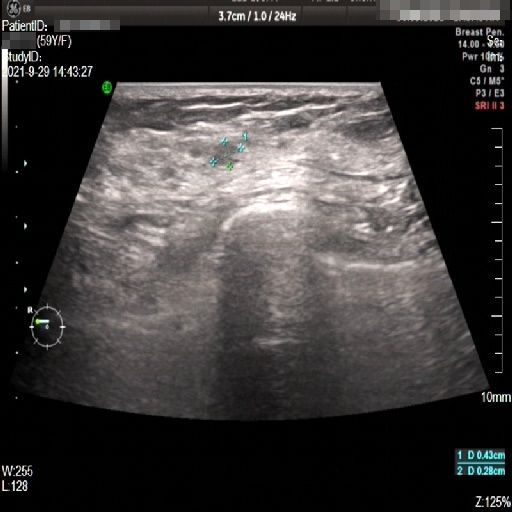

Images with certain annotations are considered noisy images in the context of the noise removal task, and corresponding images without these annotations are considered clean. Some typical images with various annotation are provided in Fig. 1.

In essence, a body marker annotation is a marker selected from a fixed set of icons that indicates different regions of the human body and its current orientation. It is typically located at the edge of the ultrasnoic image area and is labeled by the sonographer. On some ultrasound machines, the body marker annotation has a fixed position.

The radial line annotation is pairs of connected cross markers. They are usually placed at the edge of the lesion area, with its placement determined by the size of the lesion. One to three pairs of cross markers may be present in an image, corresponding to the three axes of 3D space, but typically there are only two pairs.

The vascular flow annotation is not an additional labeling feature meant to simplify identification. Rather, it serves as a bounding box that identifies the specific area of the image being examined by the ultrasound flowmeter. However, to keep things simple, we will continue to call it a form of annotation. The presence of this annotation indicates that the relevant examination has been conducted.

Refer to caption

(a)

(b)

(c)

Figure 1: Images with various annotations. (a) body marker annotation, (b) radical line annotation, (c) vascular flow annotation.